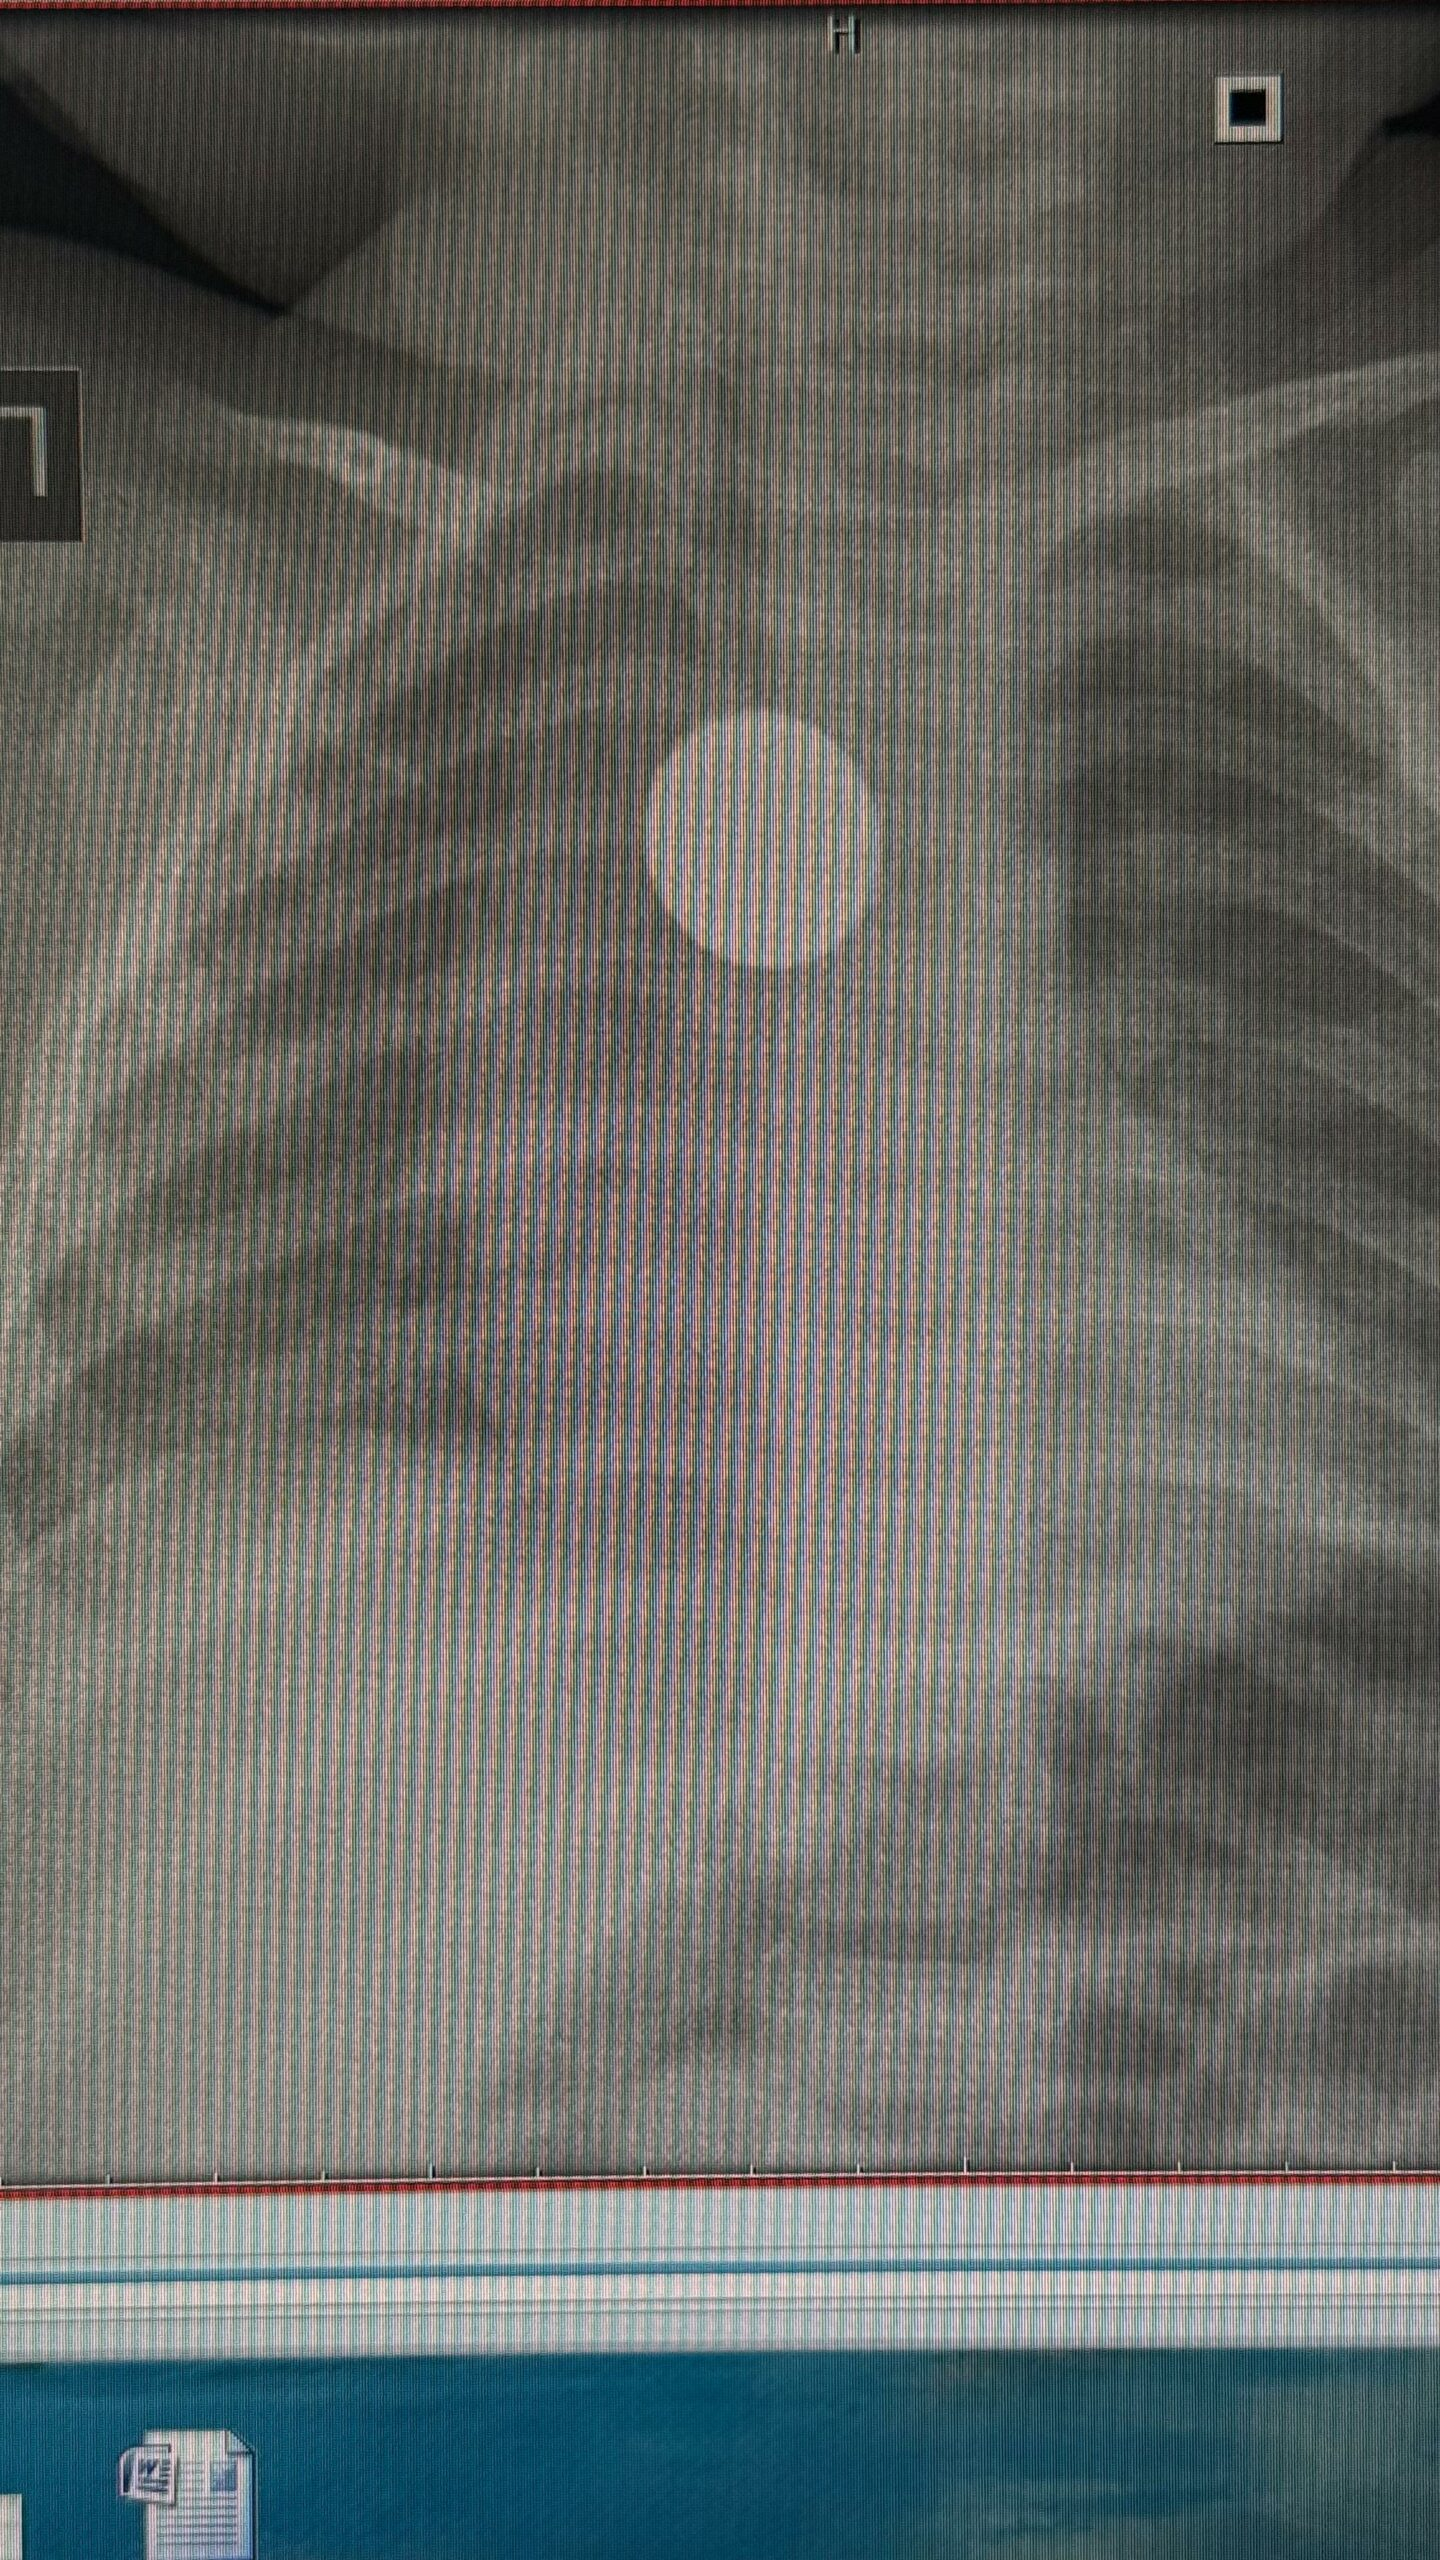

В Якутии годовалый малыш проглотил монету в пять юаней и проходил с ней целый месяц. Инородное тело застряло в пищеводе. Экстренную операцию ребенку провела врач-эндоскопист, заведующая эндоскопическим отделением РБ № 1 – НЦМ Мария Еремеева.

Монету в пищеводе годовалой девочки обнаружили случайно. Ребенка беспокоил кашель на протяжении месяца, врачи назначили рентген легких.

«Ребенка доставили в Якутск из Чурапчинского района. Монету обнаружили в области средней трети пищевода. Нам удалось вытащить инородное тело эндоскопом, ребёнок был под наркозом. У нее образовался поверхностный пролежень пищевода. Операция прошла хорошо, сейчас состояние девочки удовлетворительное», — рассказала Мария Еремеева.